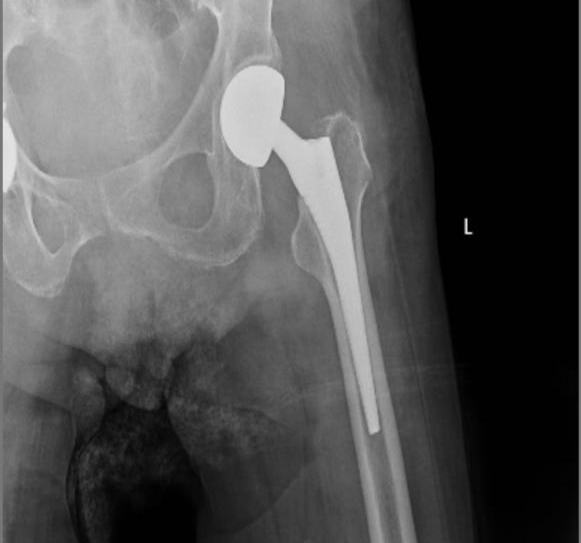

麻醉手术科团队采用“无插管静脉麻醉+腰硬麻醉”联合方式,精准控制麻醉深度,实时监测生命体征。骨科团队凭借丰富经验和精准操作,不到1小时便顺利完成人工股骨头置换术,术中出血少、创伤小。